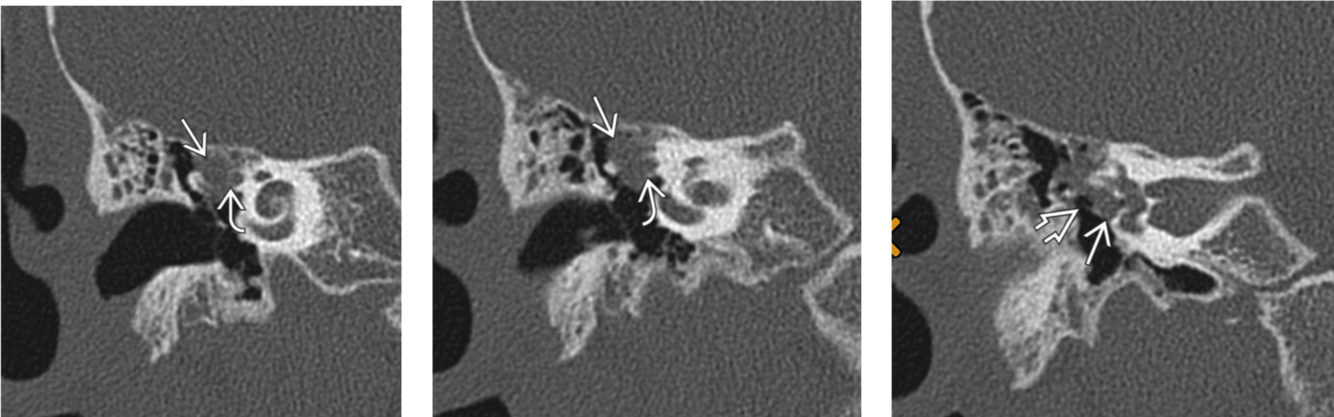

Medial epitympanic congenital cholesteatoma that erodes portions of the ossicles.

Solid arrow: choleastatoma

open arrow: erosion of the long process of the incus and hub of the stapes

Curved arrow: erosion of the lateral bony margin of the tympanic segment of the facial nerve canal

**Tympanic segment of the facial nerve will always be aberrant in the location of the oval window instead of inferior to the lateral semi-circular canal